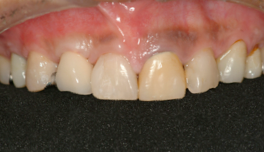

前歯の差し歯が折れて

抜歯した症例です

どの歯がインプラントかわかりません。

特に前歯のインプラントは審美性が

求められるので、

繊細な技術が必要です。